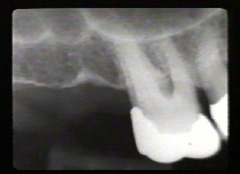

Estas

imagenes fueron producidas por Rolf Attstrom y la Asociación Dental

Dinamarquesa en colaboración con Video Goof, Dinamarca. Cámara y videoediting Tommy Ols, Videocompiling y Grabación

Anders Nattestad